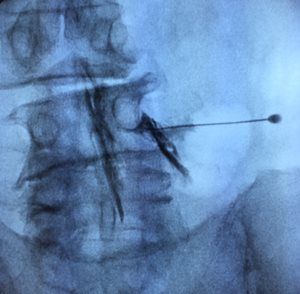

- Epidural injections with x-ray guidance

- Facet nerve blocks with x-ray guidance

- Spine facet joint injections